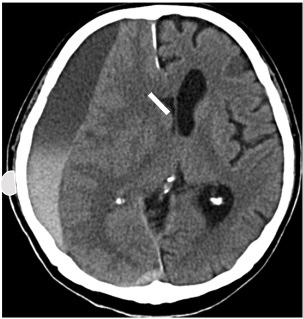

2023 A26 【問題】37歳の男性。バイク運転中にバスと衝突した。(意識状態やバイタルサインの記載なし) 搬送時の頭部CTを以下に示す。今後行うべき処置に関して正しいのを2つ選べ。

創部培養, 骨片除去